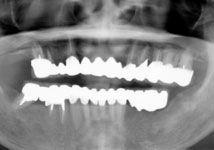

虫歯と歯周病が進行し、歯が動揺して噛みにくいということで受診されました。

歯周再生治療と審美補綴治療によってトータルコーディネートしました。

今では虫歯も治り、しっかり噛めるようになったと満足されています。 |